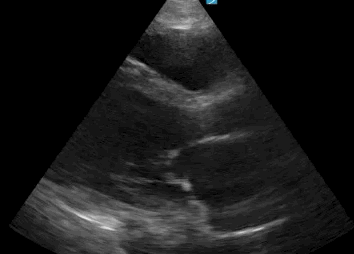

TTE - PLAX

Limited echo (TTE) - Anatomy/basics

limited echo (TTE) - Diagnostics